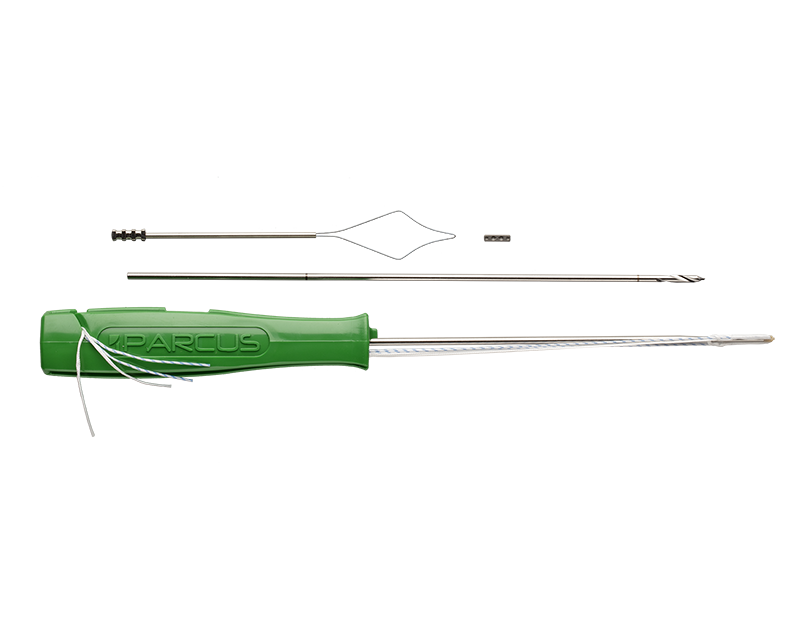

ATLAS Kit

Anatomic Thumb Ligament Arthroplasty System

Anika’s Anatomic Thumb Ligament Arthroplasty System (ATLAS) is an anatomic thumb carpal-metacarpal (CMC) reconstruction device for use as adjunct fixation of the 1st and 2nd metacarpals in CMC arthroplasty.

The ATLAS technique corrects thumb CMC instability and provides rapid return to function by placing stable suture-based anchor fixation at the anatomic insertion sites of the thumb basal ligament.

- Small insertion footprint and sub-cortical fixation for a strong, stable, bone sparing technique with 54 lbf anchor pull-out strength1